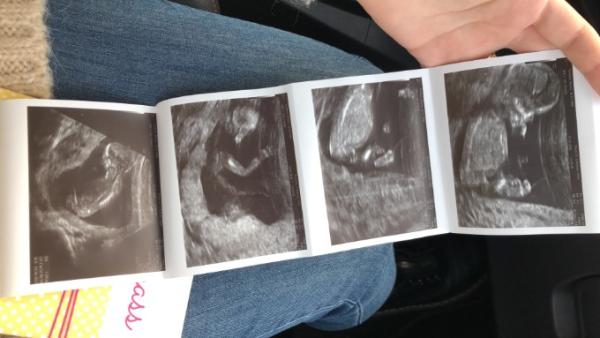

Mädels, Gestern war der Termin zum Screening. Unser Baby ist mit ganz ganz hoher Wahrscheinlichkeit gesund und vollständig ausgereift Wir sind so erleichtert. Ich wurde vom 06.06 auf den 01.06 datiert

Bild zu Nackenfaltenmessung ❤️ - Forum für Juni - Mamis

Guten morgen Die Fotos sehen toll aus, könnte man etwas zum Geschlecht sagen?

Hi, das ist doch super Richtig schöne Bilder habt ihr da bekommen Habt ihr schon eine Tendenz zum Geschlecht bekommen? Liebe Grüße